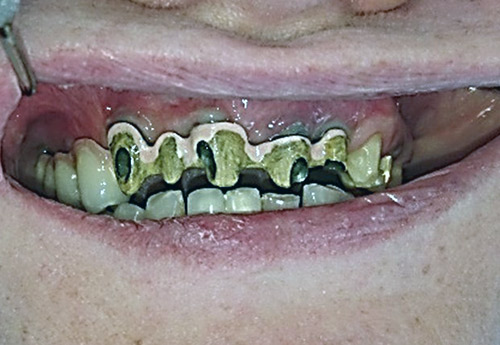

2. PHASE – state before making immediate impressions